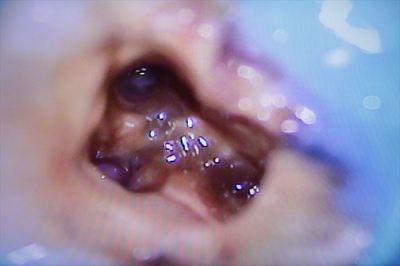

薬液洗浄後に滅菌ペーパーポイントで吸水乾燥します。